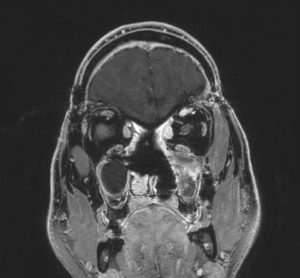

Η αξονική και μαγνητική τομογραφία εγκεφάλου ανέδειξε γιγαντιαία εξεργασία στον πρόσθιο κρανιακό βόθρο με σημαντική επέκταση εντός της ρινικής κοιλότητας και διήθηση των οφθαλμικών κόγχων, κυρίως αριστερά.

Εικόνα 1: Προεγχειρητική μαγνητική τομογραφία αναδεικνύει εκτεταμένη χωροκατακτητική εξεργασία, πιθανό αισθησιονευροβλάστωμα, με επέκταση εντός της ρινικής κοιλότητας και διήθηση των οφθαλμικών κόγχων.